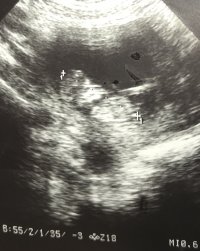

Buda 12+ 2 ultrasonu bunda görünüyormuş acaba

Son görselde ışıktan fazla etkilenmiş emin olmamakla birlikte bebeğinizin cinsiyeti kıza benziyor. Tekrar belirteyim bu haftalarda cinsiyet görülsede yanılma payı var . En net olarak 16-17-20 . haftada bebeğinizin cinsiyetini öğrenebilirsiniz.